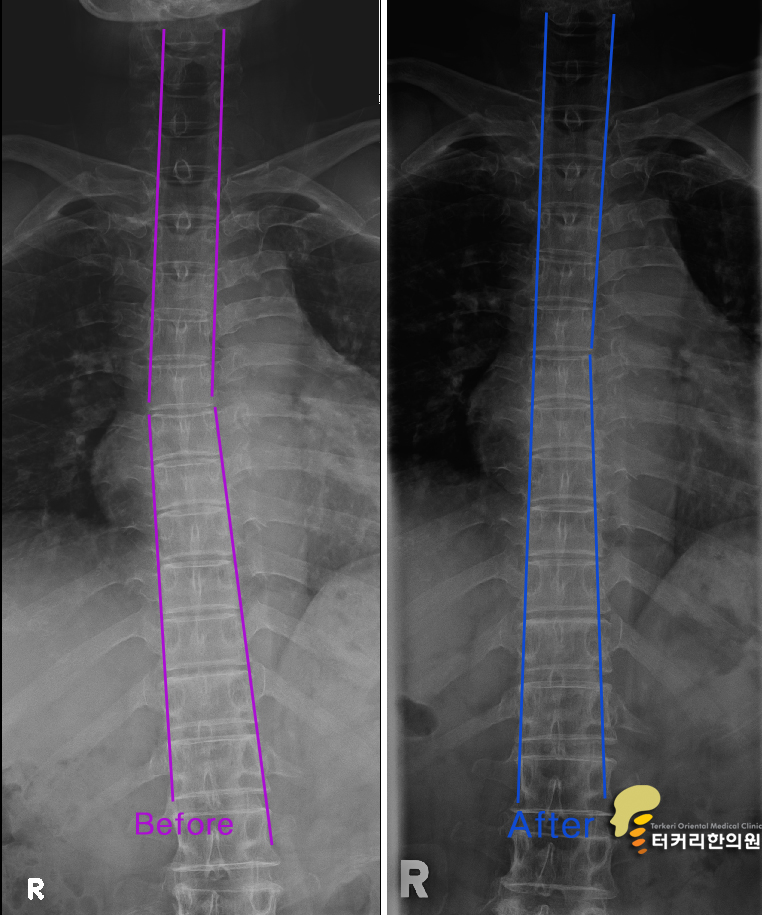

왜 그럴까요..? 척추의 교정 전과 후 척추신경은 기차이고 척추는 기찻길입니다.어느 한 위치에서 기찻길에 문제가 생기면 그 라인의 기차운행은 정지됩니다. 허리가 좁아졌다면 일자목이거나 휘어진 경추부터 C커브로 만들고 휘어진 척추도 바르게 교정을 해야 좁아진 허리 척추 간 간격이 순차적으로 벌어지게 되어 탈출된 디스크가 다시 척추사이로 들어올 수 있게 됩니다. 척추 라인이 정상으로 재조립이 되지 않고서 통증만 줄이는 치료는 매우 비과학적인 치료방법입니다. 급할수록 돌아가라허리통증이 심할수록 목, 턱관절을 치료하는 것이 24마디 모든 척추의 근본적인 치료라는 것을 반드시 명심해야 합니다. 그러므로 턱관절교정과 목교정은 척추 바로잡기의 첫 단추가 됩니다. 추간판탈출증이나 요추협착증 환자들이 30~40년을 고생을 하는 이유가 허리가 아파도 턱관절과 목을 먼저 교정을 해야 좁아진 요추의 간격이 넓어진다는 것을 모르기 때문입니다. 척추도 새롭게 인테리어를 하는 것이 진짜 치료이다.쓰러지고 좁아진 집 기둥을 새것으로 인테리어를 하듯이 추간판탈출증, 요추협착증 환자도 경추가 C커브로 바뀌어야 하고 휘어진 등도 바르게 인테리어를 받아야 좁아진 목과 허리의 간격이 넓어져서 디스크 신경의 압박을 줄이는 바른 척추 기둥으로 바뀌게 됩니다. 그렇게 하고 난 후 다시 X-ray, MRI 검사를 받아서 치료 전과 후의 결과가 달라지게 나오면 정말 척추가 새롭게 인테리어 된 것을 확인할 수 있고 이것이 진짜 척추의 치료가 된 것입니다. 이런 척추의 교정은 턱관절교정이 반드시 필요하고 신도림동 터커리한의원에서 치료를 받을 수 있습니다. 반응형'터커리' 카테고리의 다른 글병명의 개수 대로 약을 먹으면 허리디스크가 좋아질까? (102) 2024.01.09 사경증도 경추 측만증 일 뿐...교정으로 치료받자 (98) 2024.01.08 턱관절 치료는 1회용 스프린트(CBA)로 치료하자 (72) 2024.01.04 머리는 차게 배는 따뜻하게 의 중요성 (107) 2024.01.04 사경증 치료는 CBA를 이용해서 목을 척추의 중심으로 교정하는 것이 중요하다. (67) 2024.01.03